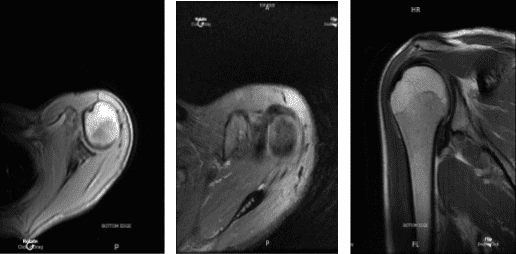

MRI Left shoulder non-contrast

The patient is a 29-year-old girl who came to see me after being involved in a car accident and complaining of an anterior shoulder ache on the left side. Physical therapy and anti-inflammatory medicines were ineffective. We performed an MRI, which revealed a type 2 labral tear.